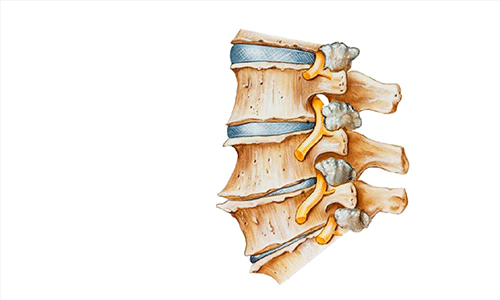

Gai cột sống là loại bệnh thoái hóa cột sống mà trong đó xuất hiện các phần xương mọc ra phía ngoài và hai bên của cột sống gọi là gai xương

Gai cột sống có thể xuất hiện ở nhiều vị trí trên xương sống của cơ thể nhưng thông thường hay gặp gai cột sống cổ và gai cột sống lưng

Hình ảnh: Gai cột sống